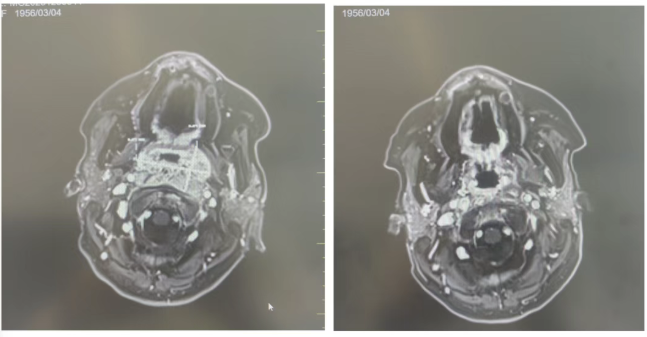

经过规范有序治疗,李奶奶病情出现明显好转。影像复查显示鼻咽部病灶接近完全缓解,肿瘤体积大幅缩小,鼻塞、鼻出血症状改善,呼吸顺畅。双耳渗出性积液逐渐吸收消退,听力显著恢复,日常交流不再困难。整个治疗过程耐受性良好,李奶奶平稳度过治疗周期,身体状态逐步向好。